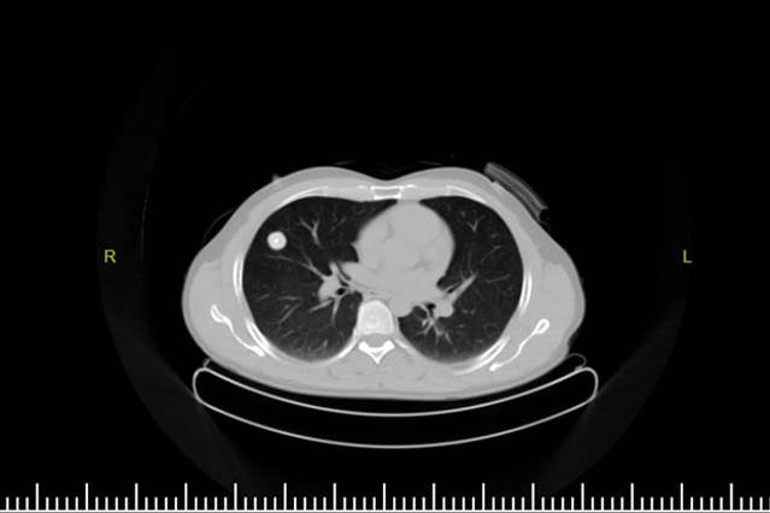

Elazığ Fethi Sekin Şehir Hastanesi Göğüs Cerrahisi Polikliniği'ne göğüs ağrısı ve öksürük şikayetiyle başvuran Topuz'un çekilen tomografisinde, sağ akciğer orta lobunda 2 santimetre büyüklüğünde tümör olduğu tespit edildi.

Hastanın yapılan takibinde akciğerindeki tümörün büyüdüğünün gözlenmesi üzerine, kanserli hücre olabileceği şüphelenilen doku operasyonla alındı.

Sağ akciğerindeki tümöre böceğin sebep olduğunu öğrenince büyük şaşkınlık yaşayan Topuz'un doktorları, ender rastlanabilecek bu durumla ilgili uluslararası makale yayınlamaya hazırlanıyor.